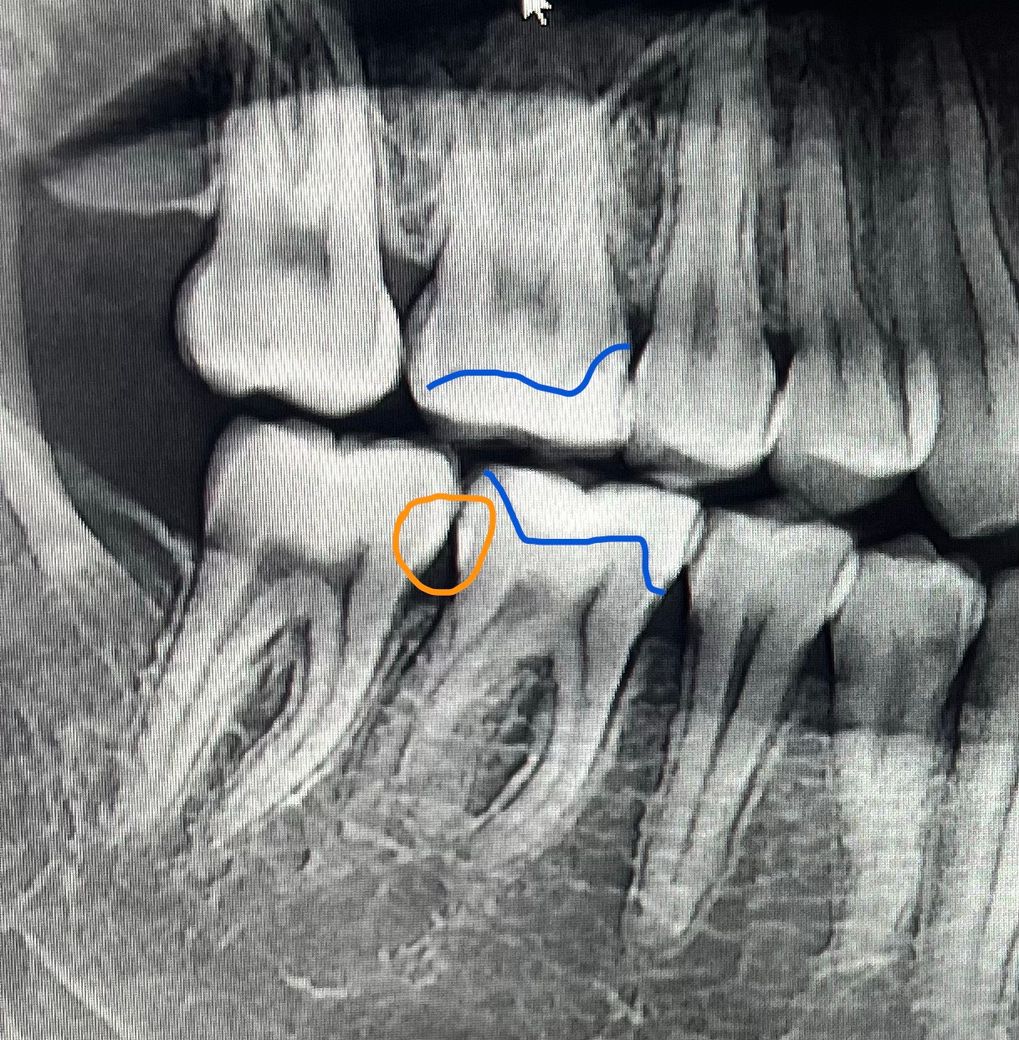

1번사진에서 주황색 동그라미 친 부분이 지금 인접면 충치가 발생한 부분입니다. 엑스레이에선 안보이나 ct에선 보인다고해요. 그리고 파란색 선이 3년전쯤 한 지르코니아 인레이 부분입니다.

현재 충치가 생긴 부분은 2번 사진에 인레이 왼쪽 인접면입니다.